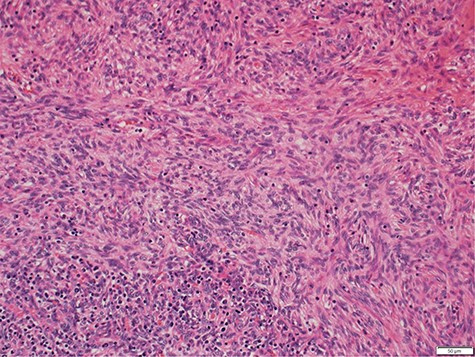

Histology demonstrated both a spindle cell component and a lymphocyte component, consistent with a type AB thymoma, and pathologic staging was pT1a (Fig. 3). Staging CT scan at this time did not reveal any other metastasis. After the successful resection of the thymoma, the patient had ongoing intravenous immunoglobulin (IVIg) infusions. She made a good recovery and was discharged home after a 3-week admission with oncology and immunology follow-up.

Photomicrograph showing medium magnification of type AB thymoma, composed of spindle cell component and lymphocyte component (biphasic tumour).